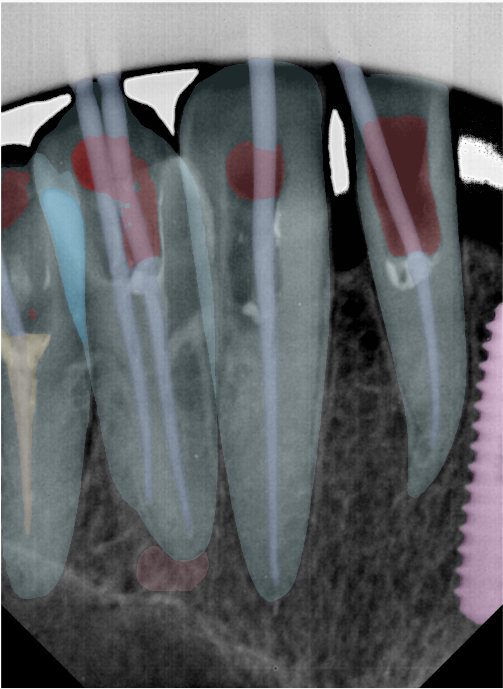

CR/DR 牙齿分割阶段记录

当前进展

- 完成了 CR/DR 牙齿相关分割训练

- 当前结果已经达到阶段预期,但仍有细节问题需要继续处理

相关测试

遇到的问题

- 训练过程中出现过 mask 下移问题

- 部分结果会出现 box 填充异常

- mask 边缘仍然有比较明显的锯齿感

参考

第二版算法问题测试

第三版算法分辨率效果比较

| 编号 | 原图 | 第一版 | 第二版 | 第三版 1216x1600 | 第三版 768x1024 | 第三版 1120x1120 |